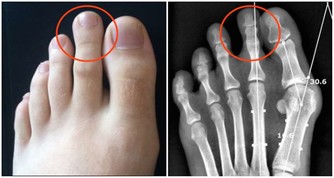

2. 神經根型:是指椎間盤突出或者骨贅壓到了神經根,症狀一般為頸部疼痛,手指麻木、皮膚感覺能力減退,嚴重者還可出現手的大小魚際和骨間肌萎縮。